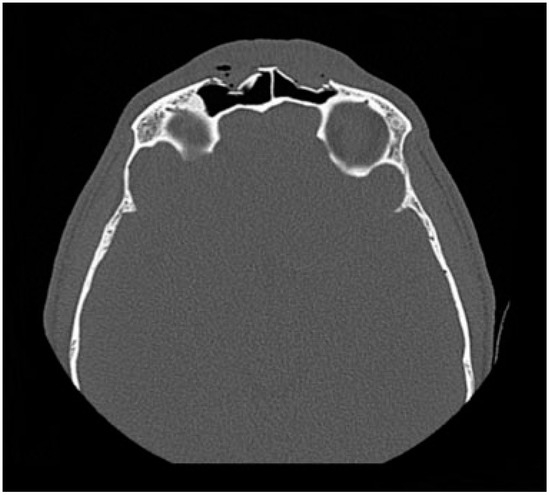

Fractures isolated to the anterior table account for 18–27% of frontal sinus fractures.[3,5,16] The indication for repair has mainly focused on correcting a cosmetic deformity. Without injury to the frontal sinus outflow tract or posterior table, many series have reported on the safety of observation of isolated anterior table fractures.[1,3,4,17,18] The degree of displacement necessitating repair is controversial. The degree of displacement seen on CT imaging may not correlate with the either the visualized or palpated deformity due to overlying edematous soft tissue. It is also difficult to predict the degree of resultant deformity after the acute swelling subsides (Figure 2). Furthermore, physician and patient expectations vary regarding the definition of an “acceptable” forehead contour. With observation, bony remodeling and scarring over an intact periosteum may subsequently hide any cosmetic deformity, especially in pediatric patients [19].

Figure 2. CT in the axial plane demonstrating a comminuted, displaced bilateral fracture of the anterior table of the frontal sinus fracture. In the acute setting, significant soft tissue edema may obscure a palpable deformity.